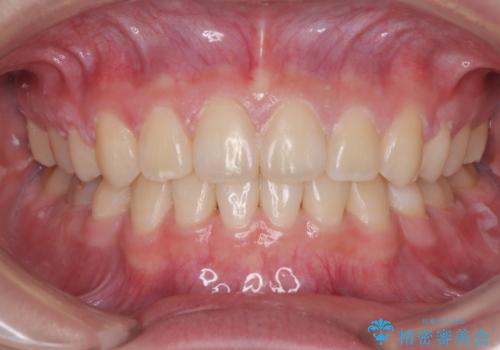

目立たない装置でデコボコを改善 ハーフリンガルによる矯正治療

- 上下顎歯列のデコボコを改善したいとのことで来院された患者様です。

自己管理の大変なインビザラインや、目立つ表側のワイヤー矯正は避けたいとのことで、

上顎だけ裏側装置のハーフリンガルにて矯正しました。

一年と数か月で矯正を終えることができました。

下顎前歯部には後戻り防止のワイヤーを装着しています。